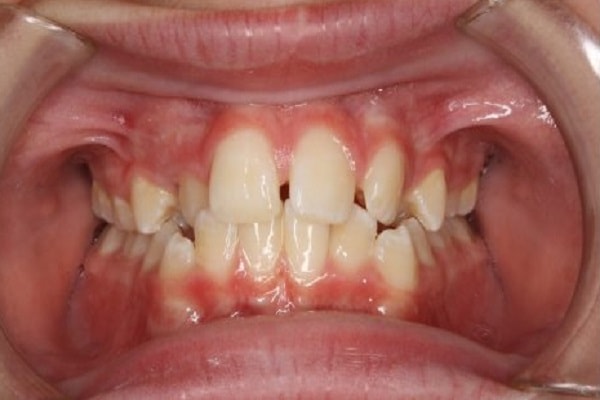

Dental braces are orthodontic devices used in methods to align teeth, straighten crooked or crowded teeth, and treat gaps and other orthodontic problems between teeth.

People are usually fitted with braces by orthodontists, but some general dentists can also do this. Misaligned teeth are not just aesthetic problems. Crooked teeth can greatly increase the likelihood of gum disease. If left untreated, it can lead to tooth loss, receding gums, chronic bad breath and bleeding gums.

Many types of braces are available. Which one is best for you depends on the nature and severity of your orthodontic problem and your personal preference.